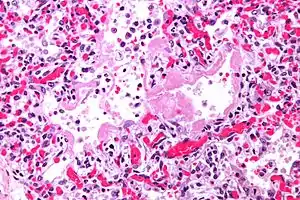

Micrograph of diffuse alveolar damage, the histologic correlate of acute interstitial pneumonitis. H&E stain.

Rapid progression from initial symptoms to respiratory failure is a key feature. An x-ray that shows ARDS is necessary for diagnosis (fluid in the small air sacs (alveoli) in both lungs). In addition, a biopsy of the lung that shows organizing diffuse alveolar damage is required for diagnosis. This type of alveolar damage can be attributed to nonconcentrated and nonlocalized alveoli damage, marked alveolar septal edema with inflammatory cell infiltration, fibroblast proliferation, occasional hyaline membranes, and thickening of the alveolar walls. The septa are lined with atypical, hyperplastic type II pneumocytes, thus leading to the collapse of airspaces. Other diagnostic tests are useful in excluding other similar conditions, but history, x-ray, and biopsy are essential. These other tests may include basic blood work, blood cultures, and bronchoalveolar lavage.